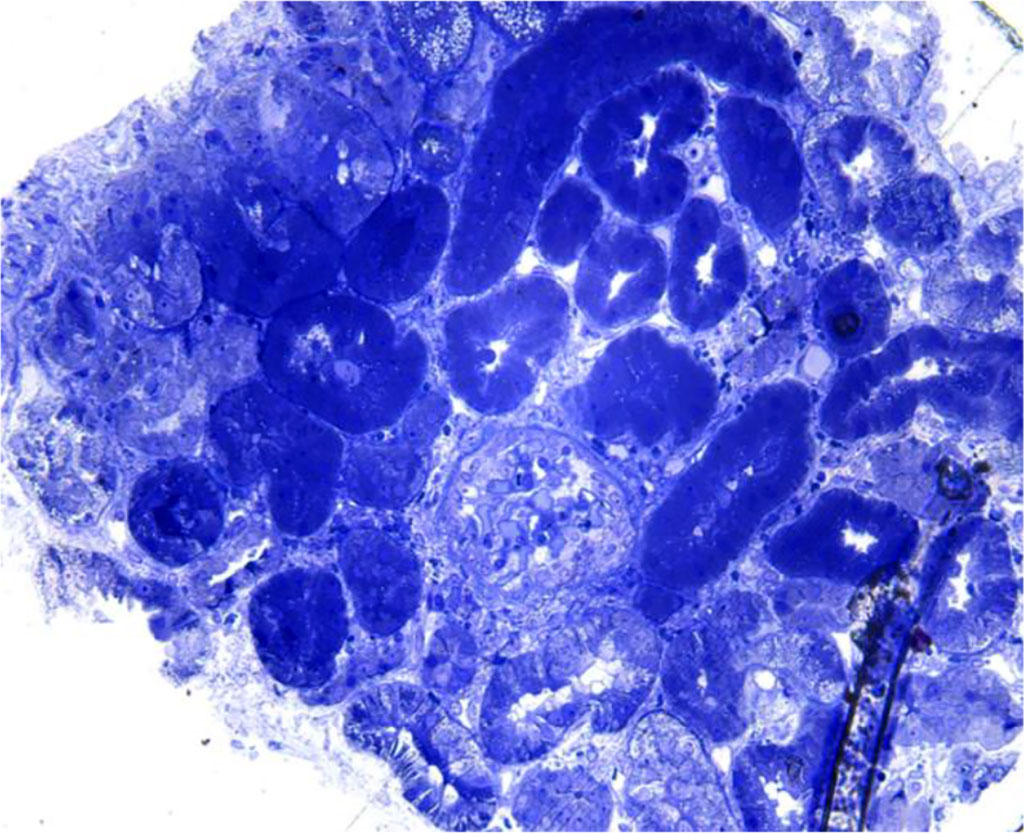

Figure. 1 Light microscopy- Severe interstitial hemorrhage in the medulla without interstitial inflammatory reaction

Figure 2. Light microscopy- glomerular sclerosis; periglomerular lymphoplasmocytic inflammation

Figure 3. Light microscopy – absence of interstitial hemorrhage in the renal cortex

Renal biopsy is an invasive technique that is done to establish the exact diagnosis and choose the right treatment. In our case, the renal biopsy gave us an important information: interstitial hemorrhage in the medulla, which is highly suggestive for hantavirus nephritis. Renal hemorrhage can be found in some different situations (Table 1) [1].

Returning to the case of our young man, we can exclude acute transplant rejection because the patient is not transplanted; a renal infarction or renal vein thrombosis would have been objectified on the CT examination of the abdomen and pelvis; and a post-procedural complication would have been highlighted following the ultrasound control performed 24 hours after the renal biopsy. Thus, the hemorrhage encountered in the renal medulla and not in the cortex, directs our diagnosis to a viral infection.

The first cases in Romania of hemorrhagic fever associated with renal syndrome were described in 1976 and included 11 patients (10 men and 1 woman). The pathogen was not identified at that time, but there was a strong suspicion that it was a virus. The patients reported came from similar geographical areas – mountain areas (Tranylvania region - Abrud, Miercurea Ciuc, Odorheiul Secuiesc), which could be a reservoir of infection. Of all, 2 patients died in the first hours after admission, 9 patients gradually recovered their renal function, 4 patients required hemodialysis and 4 patients fully recovered renal function at 1 year. The symptoms were characterized by fever, chills, headache, intense muscle pains, hemorrhagic syndrome (gum bleeding, epistaxis, hematemesis, melena) followed by gastrointestinal symptoms and renal symptoms (non-selective proteinuria of 2 to 15 g/day and hematuria). Histological informations were obtained from the autopsies of the two fatal cases and from the renal biopsies performed in seven of the surviving patients. The autopsies showed intense hemorrhages spreading over the pyramids and light microscopy revealed intense congestion in the renal pyramids and prominent hemorrhages within the tubules and interstitium [7].

An important way to confirm hantavirus infection is by renal biopsy. The histological findings in hantavirus nephritis are peritubular capilaritis without important tubulitis and hemorrhage is limited in the medulla [5]. Interstitial oedema and inflammatory cell infiltrates (lymphocytes, monocytes, macrophages and polymorphonuclear leucocytes) are usually seen. In electron microscopy, podocytes foot process effacement was described in some studies with hantavirus infection [9,10]